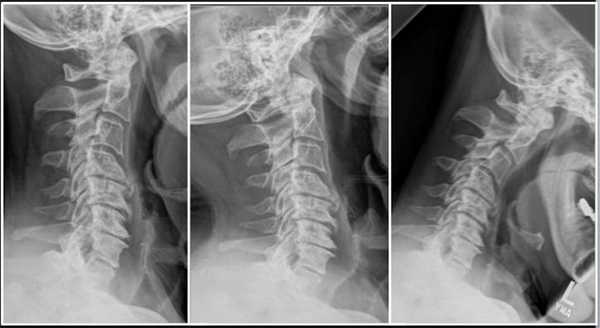

Шейный (цервикальный) отдел - самая подвижная часть позвоночной системы, имеющая изначально узкий позвоночный канал и богатую нервно-сосудистую сеть. Его позвонки отличаются мелкими размерами и специфичным строением, при этом мышечный каркас, который осуществляет поддержку и работоспособность шейных элементов позвоночника, анатомически недостаточно сильный и выносливый. Все это объясняет широкую распространенность возникновения именно в этой хребтовой зоне различного рода дегенераций и травматических повреждений, характеризующихся яркой неврологической симптоматикой.

Строение шейного отдела позвоночника.

Однако большую тревогу вызывает тот факт, что шейные патологии часто сопровождают очень серьезные последствия, среди которых парез и паралич конечностей (особенно рук). Кроме того, запущенные формы болезней могут провоцировать тяжелую дыхательную недостаточность, стремительное ухудшение зрения и слуха, острое нарушение кровообращения в тканях головного мозга и пр. Поэтому лечение цервикальной зоны позвоночного столба предельно важно начинать как можно раньше, как только человек почувствовал первый дискомфорт в соответствующей области.

В противном случае заболевание примет агрессивный характер, что приведет к сильному сужению спинального канала, защемлению нервных корешков и/или пережиму артерий, возможно, к поражению спинного мозга со всеми вытекающими последствиями. Тяжелые состояния лечатся исключительно хирургическим путем.

Ущемление позвоночного канала вледствие выпячивания диска.